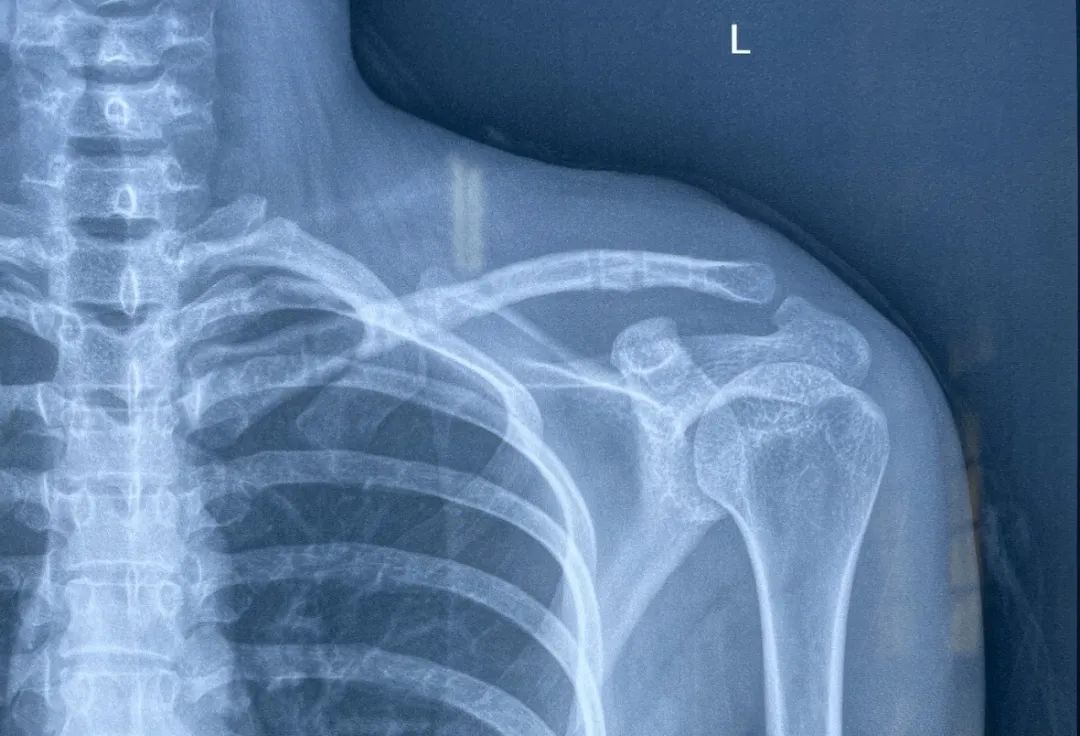

患者:女,28 岁。左肩部疼痛伴活动受限 3 天。

1 年前摔伤致左锁骨中段骨折,行切开复位钢板内固定。1 个月前 X 线片提示骨折断端已愈合。

给予内固定取出术,术后复查 X 线:

患者 3 天前无明显诱因出现左肩部疼痛伴活动受限。

查体:左锁骨中段压痛、叩击痛阳性,局部可见畸形。遂以「左锁骨骨折术后再发骨折」收治入院。拟行手术治疗。